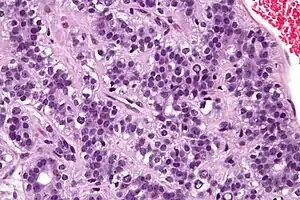

| Micrograph of an adenomyoepithelioma. H&E stain. | |

An adenomyoepithelioma of the breast is a rare tumour in the breast composed of glandular elements (adeno-) and myoepithelial cells. It is usually benign;[1] however, there are reports of malignant behaviour.[2]

The histomorphologic appearance can mimic invasive ductal carcinoma, the most common type of invasive breast cancer.